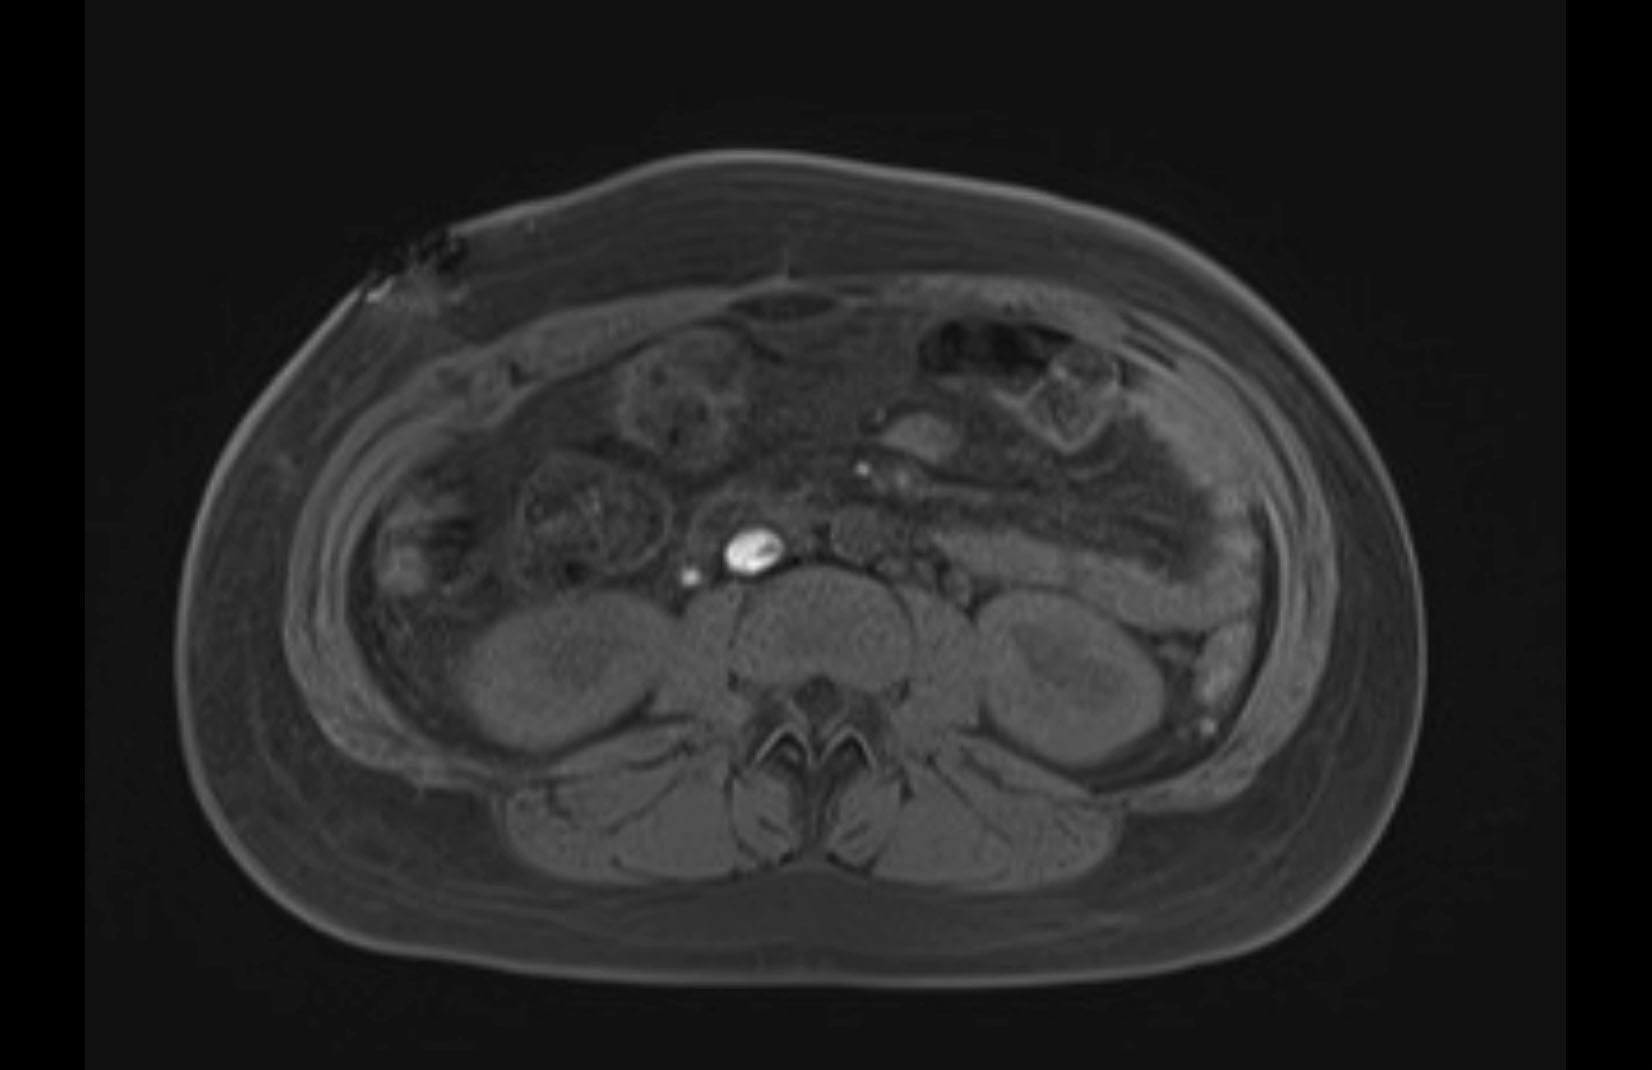

Imaging Analysis

Look through the patient's CT scan to identify any areas of concern for the necessary procedure.

MRI T1